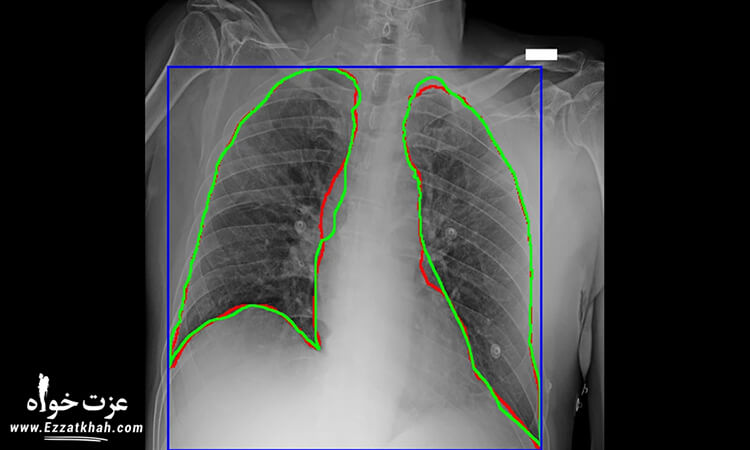

« ما شاهد تحولی عظیم در نحوه تشخیص بیماری در طول یک سال اخیر بوده ایم، از تجزیه و تحلیل تصویری ایکس ری با دستگاه های خود آموز گرفته تا توسعه در سرعت و کیفیت کیت های تشخیص بیماری که مستقیماً به دست مشتری می رسند، » به نقل از دکتر وین گوپتا، پزشک سرپرست تیم واکنش به کووید 19 آمازون.

برنامه توسعه تشخیص دهی AWS باعث سرعت بخشی به پروژه هایی شده است که تأثیر مستقیمی بر تشخیص کووید 19 داشته اند، در همین راستا اقداماتی که با تشخیص پزشکی ممکن هستند، به کلی متحول شده اند.